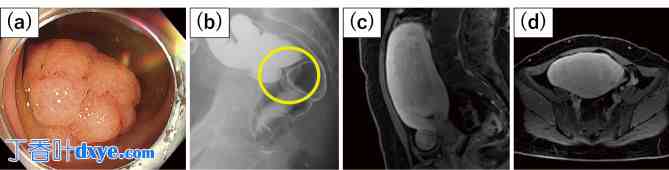

患者为一名45岁女性,既往无特殊病史。她因便血就诊。身高158.5厘米,体重70.9公斤,BMI为28.22。血液检查显示重度贫血,血红蛋白为8.6克/分升。下消化道内镜检查和造影灌肠检查发现腹膜反折上方直肠内有直肠癌(图1(a)、(b))。组织活检确诊为腺癌。磁共振成像(MRI)检查还发现子宫巨大肌瘤,最大直径达18厘米(图1(c)、(d))。术前诊断为直肠癌,cT2N0M0,c期I期,合并巨大子宫肌瘤。严重贫血的原因可能是巨大的子宫肌瘤,它可能阻塞了盆腔手术视野,因此作者计划同时进行直肠和子宫切除术。由于机器人手术在盆腔内操作灵活、创伤小且美容效果好,作者选择机器人手术而非开放手术。手术方案是先切除巨大的子宫肌瘤,然后再切除直肠癌。套管针的放置如图2(a)、(c)所示。目标区域设定在盆腔中心,左右两侧的套管针根据手术入路方向互换。子宫肌瘤朝向宫颈,作者从两侧入路,并使用血管封闭器切断子宫阔韧带(图2(b)、(d))。宫颈通过腹腔侧面使用单极弯剪进行分离(图3(a)、(b))。将 GelPOINT Access Platform™(Applied Medical 公司)连接至阴道(图 4(a))。从腹腔和阴道两侧确认子宫与直肠的边界(图 4(b)),并安全地实施了单纯全子宫切除术。用倒刺缝线缝合分离的宫颈残端(图 3(c))。

图 1.

下消化道内镜检查、灌肠造影结果和钆增强 MRI 结果。

(a) 下消化道内镜检查显示直肠内存在 I 型肿瘤

(b) 灌肠造影显示直肠内存在肿瘤(圆圈所示)。

(c) (d) 钆增强 MRI 显示子宫内存在巨大肌瘤,最大直径达 18 cm。